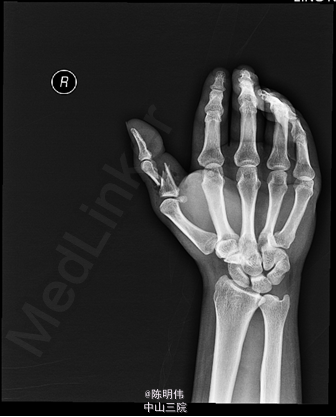

右拇指正侧位示:右拇指近节指骨中段可见斜行骨折线影,骨折两端明显成角及错位,其周边软组织肿胀;